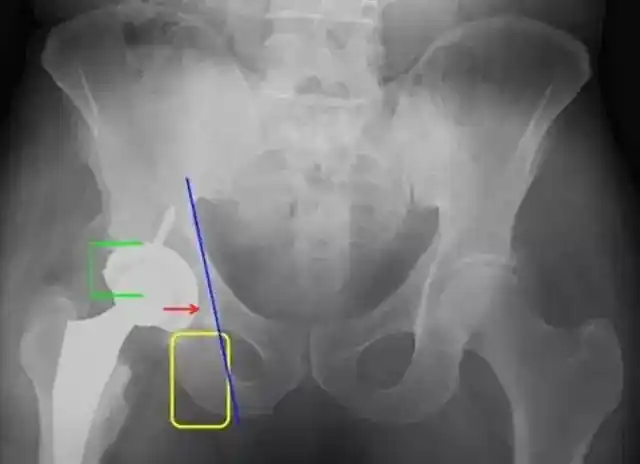

有一种痛叫髋关节撞击综合症,有一种痛叫髋臼盂唇损伤

aaos2017髋臼骨缺损paprosky分型及处理方法

成人髋臼发育不良ppt

髋臼盂唇损伤示意图(来自mayoclinic)